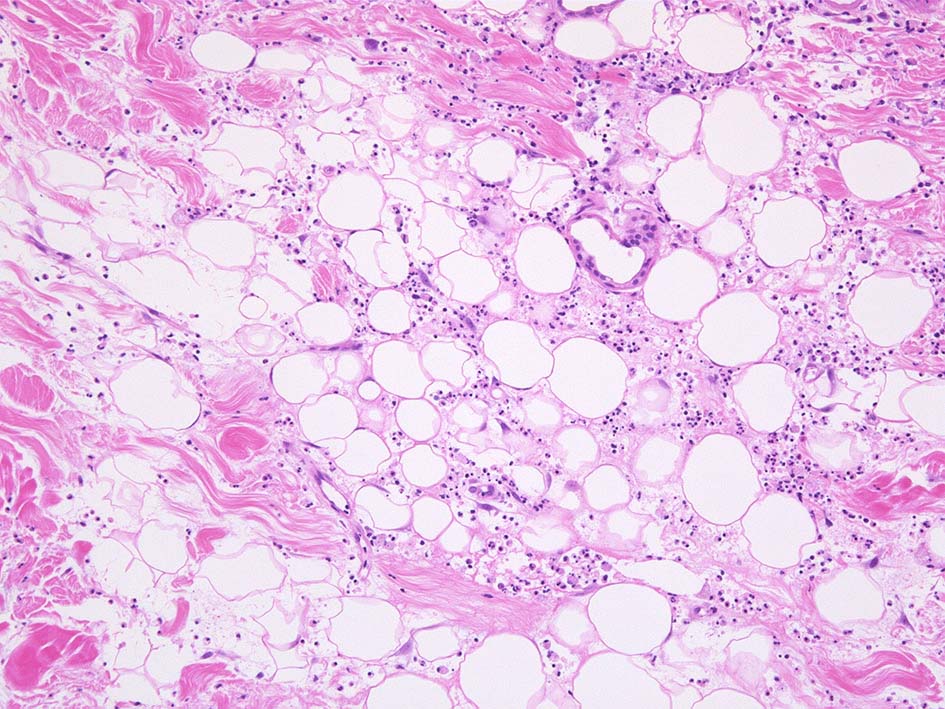

HE x40. 表皮下水疱あり. 真皮上層は浮腫状. 真皮から皮下組織にかけて, 多数の好中球が浸潤している. リンパ球, 好酸球が混在, 核破砕物を貪食するマクロファージが増加. 膠原線維にはところどころ変性が見られる.

真皮上層には核破砕物が多く, 好中球浸潤が認められる. 慢性炎症性細胞も浸潤している.

フィブリノイド壊死を呈する血管炎は認められない.

皮下脂肪織炎病変には局所的なhemophagocytosisが認められる. 血管にはfibrinoid necrosisは見られない。